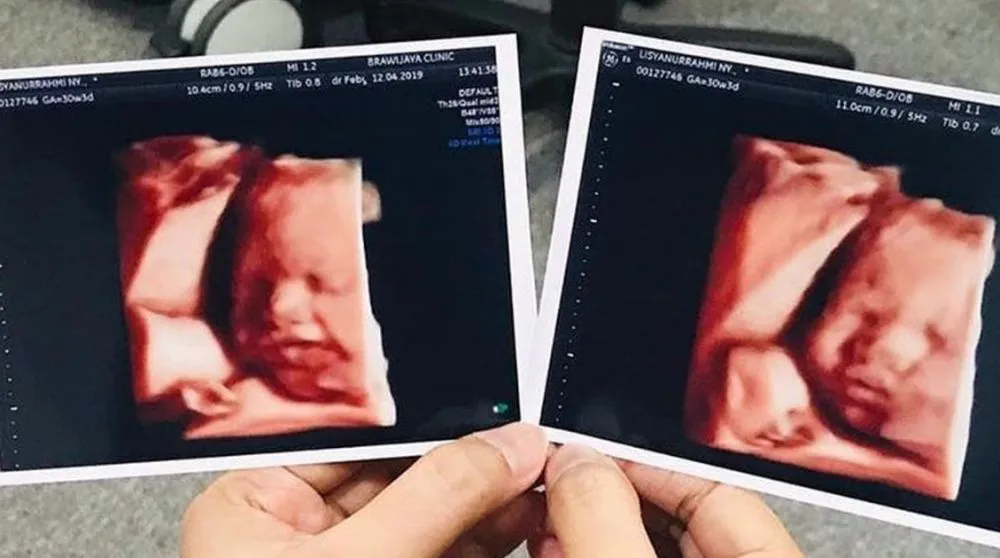

Pemeriksaan USG dilakukan untuk membantu dokter memeriksa perkembangan janin maupun organ kewanitaan selama masa kehamilan. Lewat USG juga bisa diketahui jenis kelamin si buah hati. Tak hanya itu saja, lewat USG juga bisa mengambil pose bayi saat di dalam kandungan.

Tak mau ketinggalan momen kehamilannya, para selebriti Tanah Air juga mengabadikan potret buah hati saat melakukan USG. Menariknya, gambar anak seleb saat di kandungan ini punya pose yang unik.

Penasaran seperti apa potretnya? Dilansir brilio.net dari berbagai sumber, Rabu (15/4), berikut penampakan USG calon bayi para seleb.